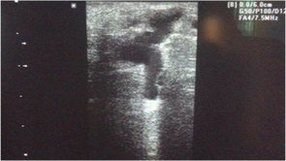

Resim. Perforan vende çap artışı ve dopplerde kaçak